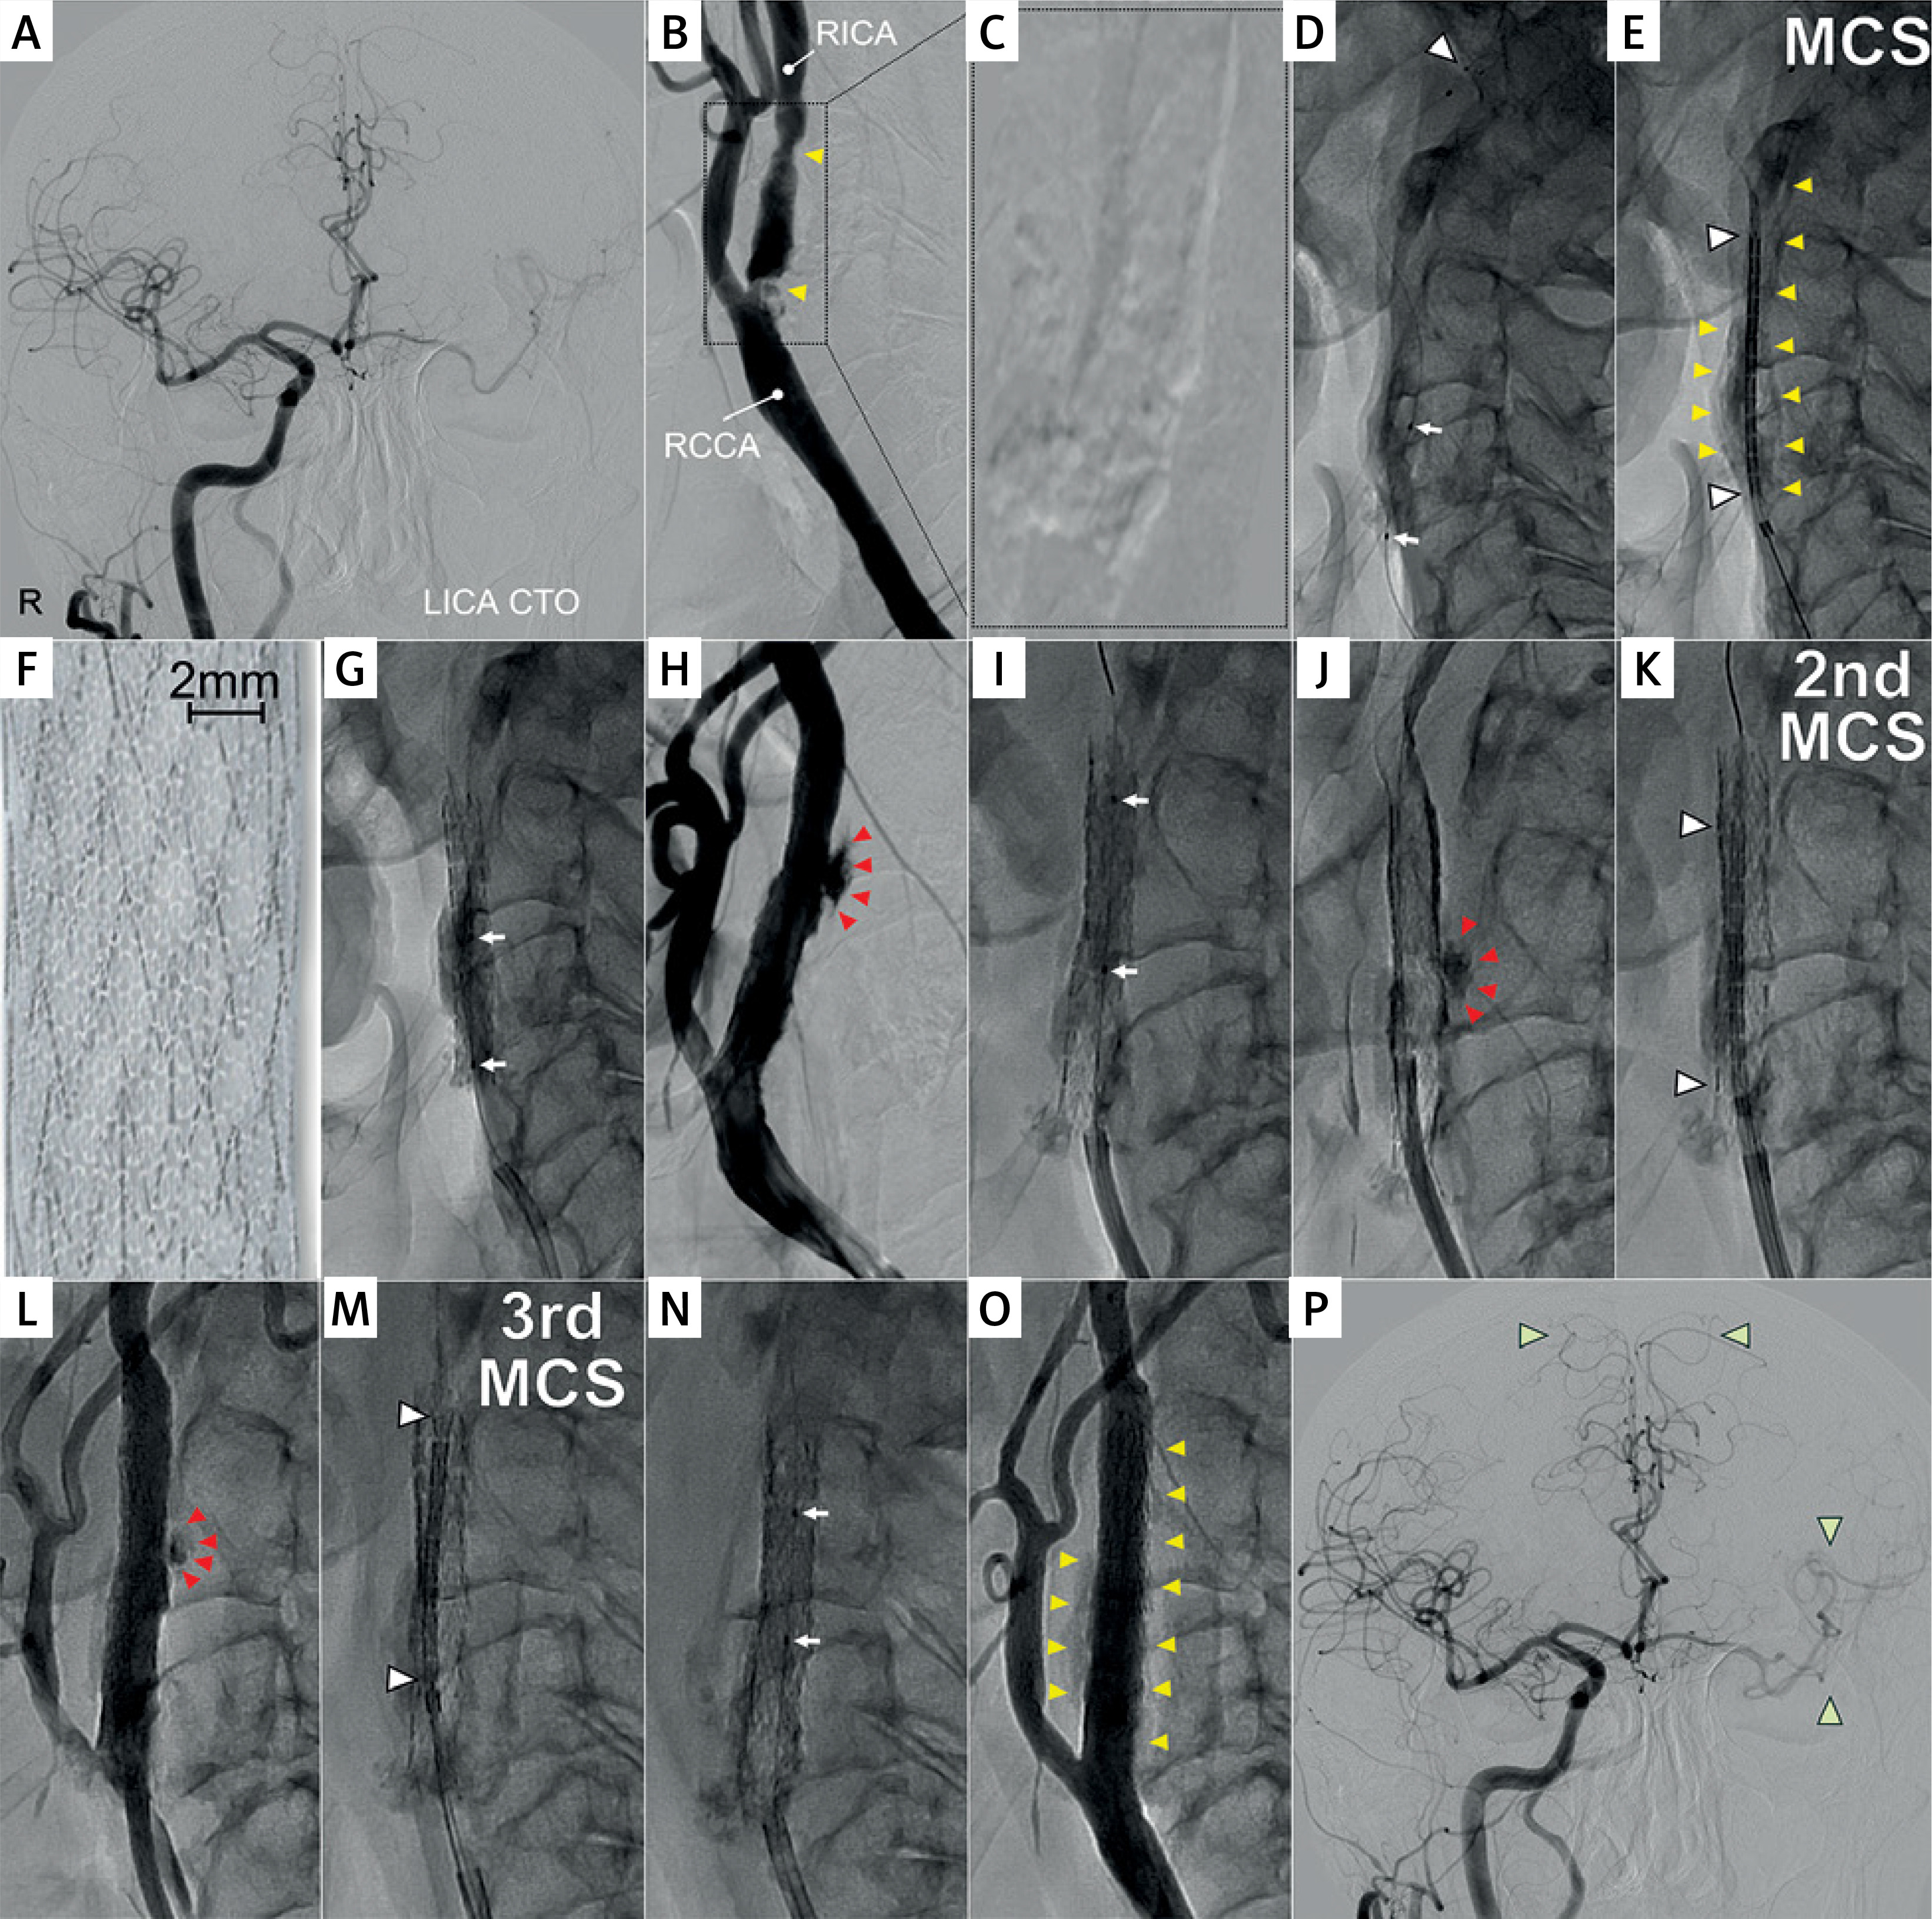

We would like to share our use of a MicroNET-covered stent-in-stent implantation (‘sandwich’ technique, Figure 1) to seal carotid artery perforation, a rare complication of CAS [12], which occurred during treatment of a highly-calcific carotid lesion in an acute carotid syndrome patient who was rejected from surgery.

Figure 1

Procedural images demonstrating the MicroNET-covered stent ‘sandwich’ technique to seal calcific carotid artery perforation. A is a baseline cerebral angiogram in a 64-year-old male diabetic patient with left internal carotid artery (LICA) chronic total occlusion (CTO; past left-hemispheric stroke, mRS 2) and a symptomatic highly-calcific carotid stenosis on the right (recurrent transient ischemic attacks), cleared by the Neuro-Vascular Team for endovascular management rather than surgery due to severe heart failure, neurologic consequences of prior left hemispheric stroke, and multiple co-morbidities; B shows the right common carotid artery (RCCA) distal non-obstructive diffuse lumen defects and a tandem (yellow arrowheads) stenosis of the right internal carotid artery (RICA) with critical severity in the proximal portion (note projecting calcific nodules); C is a zoomed non-contrast image of the treatment target zone; note massive calcifications forming a calcific “cast” of the index carotid bifurcation (Grade 4 severity of calcifications; circularity index 4 [9]), extending to the proximal right external carotid artery and involving a long segment of RICA (cf., E); D predilatation of the proximal (tight stenosis) portion of the tandem lesion (preceded by placement of a neuroprotective filter in distal RICA – Spider FX 7.0 mm, white arrowhead); initially 3.0 × 12 mm non-compliant (NC) balloon was used, followed by 4.0 × 15 mm NC balloon and 4.5 × 15 mm NC balloon (step-wise carotid calcific lesion preparation as per the PARADIGM Study HCCS Management Protocol [9, 11]); E shows positioning of a MicroNET-covered neuroprotective self-expandable stent (CGuard 9.0 × 40 mm); note that the stent insertion through the distal portion of the tandem required predilating also of the angiographically non-critical distal stenosis; yellow arrowheads denote angiographically-evident calcifications; F is a photograph of the MicroNET-covered stent, consisting of a widely open-cell (area of ~22 mm2, ensuring high adaptability) laser-cut nitinol frame that is wrapped into an embolic prevention MicroNET sleeve (microcell size ~0.02–0.03 mm2) positioned outside the stent frame [18, 19, 21, 22]; G shows post-dilatation optimization of the proximal portion of stented lumen, using a 5.5 × 15 mm NC balloon (arrows denote balloon markers); this step was preceded by sequential embedment of the stent with a 5.0 × 20 mm NC balloon; H is a dye injection demonstrating a focal perforation (red arrowheads) in the mid portion of the stent, causing contrast extravasation; I shows a sealing attempt by performing low-pressure balloon inflations (arrows denote balloon markers); J demonstrates lack of efficacy, in this case, of balloon sealing as the first-line management (red arrowheads point to continued contrast extravasation); note that this angiographic evidence of perforation was accompanied by gradual formation of a neck hematoma; K is implantation of the 2nd MicroNET-covered stent (stentin-stent ‘sandwich’ technique; CGuard 8.0 × 30 mm, white arrowheads) to increase the sealing density effect; this was followed by a gentle balloon inflation to optimize the apposition of the sealing layers; L is a control angiogram demonstrating a reduction – but not yet cessation – of contrast extravasation (red arrowheads); M shows implantation of the 3rd MicroNET-covered stent (CGuard 8.0x30 mm; stent-in-stent-in-stent, white arrowheads) to further maximize the perforation sealing; N is the final balloon inflation for optimized embedment of the 3 (stent + MicroNET) layers; O shows an optimal final angiographic result at the target lesion level of a stenosis-free reconstruction of the target vessel supplying both the right and left cerebral hemisphere; P is the final end-organ angiogram, demonstrating improved cerebral perfusion (white arrowheads, cf., A) in absence of any procedure-related neurologic symptoms

In contrast to the previously reported [13] effective sealing of perforation in a non-diseased carotid artery with a single MicroNET-covered stent, sealing of the highly-calcific internal carotid artery required creating a layer of 3 MicroNET-covered stents; a new interventional solution (Figure 1). 12-month clinical follow-up was normal, and computed tomography angiography and Duplex ultrasound showed an optimal anatomic and functional effect and, despite the 3 stent + MicroNET layers, with luminal flow normal for a single MicroNET-covered stent and absence of any in-stent restenosis (Figure 2). This is consistent with the MicroNET-covered stent normal healing [22, 24–26], and a lasting effect of optimal endovascular reconstruction of carotid artery perforation using a MicroNET-covered stent-in-stent technique, in agreement with a lasting mid-term and long-term effect of MicroNET-covered stent use to restore normal carotid artery lumen in elective stroke prevention and in emergency treatment of carotid-related stroke [11, 22, 24–26].

Coiling, an endovascular equivalent of surgical ligation, is associated with a greater stroke risk than that seen with reconstructive techniques that maintain vessel patency and thus ipsilateral cerebral supply [13]. Target artery sacrifice was not considered an option in our patient with a chronic occlusion of the contralateral carotid artery (Figure 1).

We report effective and uncomplicated sealing of iatrogenic carotid artery perforation using a MicroNET-covered stent ‘sandwich’ technique (Figure 1) with a lasting, optimal angiographic and clinical result (Figure 2). This result is consistent with accumulating evidence for optimal short- and long-term outcomes with the MicroNET-covered stent system in treatment of carotid artery thrombo-atherosclerotic disease in stroke prevention and in acute stroke [5, 11, 20–22, 25]. Still, operators should be fully aware that the MicroNET-covered stent system is not fully-covered (i.e., it is not a stent graft). Thus, in case of potential incomplete sealing of the leak with a single MicroNET-covered stent [13] or using the MicroNET-covered stent ‘sandwich’ technique (Figure 1), stent grafts [31] should continue to be available on-shelf for major ruptures that may not be amenable to sealing with the micro-porous MicroNET-covered stent(s). While use of scoring balloons and cutting balloons for calcium rupture more ‘controlled’ than that occurring with non-compliant balloons [8] may increase the safety of highly-calcific carotid lesion CAS [11], use of ultrasonic pulse waves to micro-fracture calcium deposits in the vessel wall (thus turning a non-compliant lesion into a compliant one) is particularly promising [8, 33].

In conclusion, we have demonstrated a safe and effective use of a MicroNET-covered stent system ‘sandwich’ technique to resolve iatrogenic carotid artery perforation of a highly calcific stenosis (Figure 1) in absence of any in-stent restenosis (Figure 2).